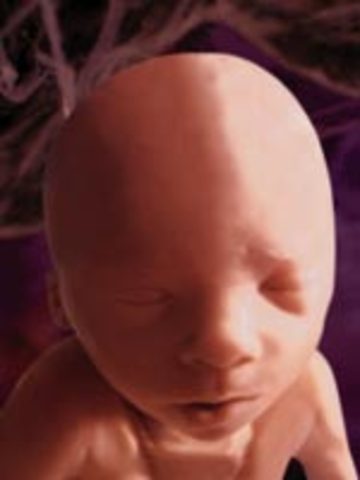

• week12

week12

1.The fetus starts moving spontaneously

2.The face is beginning to look like a baby's face

3.The fetus can suck their thumb, and get hiccups

4.The pancreas is functioning and producing insulin